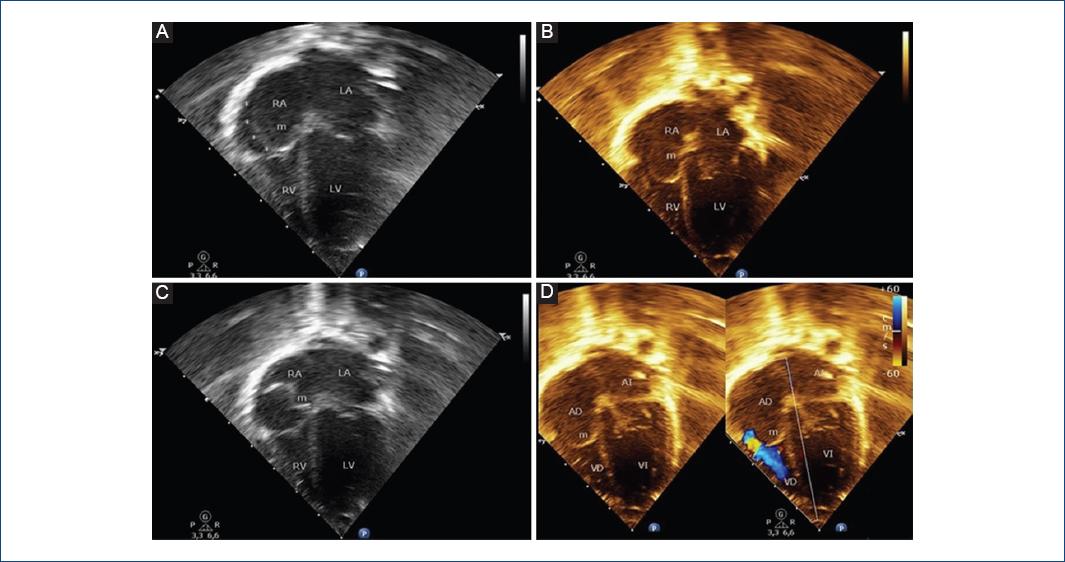

We present the case of a term newborn, with no significant perinatal history, who was taken to the emergency room at 18 days old for intermittent episodes of cyanosis, with no signs of respiratory distress, oxygen saturation of 85%, arterial gases with moderate hypoxemia, and normal chest X-ray. The transthoracic echocardiogram (TTE) revealed a large undulating membrane that divided the right atrium into two chambers and partially prolapsing through the tricuspid valve (Fig. 1A-D and Video 1). The caval veins drain into the posteromedial chamber, with part of its flow redirected by the membrane to the left atrium through the foramen ovale (Fig. 2A-D and Video 2). Contrast with an agitated saline solution was performed, observing initial accumulation of microbubbles in the posteromedial chamber (Fig. 3A-B).

Figure 1 Apical four-chamber transthoracic echocardiographic images. A-C: Illustrating a membrane (m) that divides the right atrium into two chambers and partially prolapsing through the tricuspid valve. D: Echocardiographic image with color Doppler shows eccentric flow through the tricuspid valve from the outer part of the right atrium to right ventricle (with no significant gradient). RA: right atrium; LA: left atrium; RV: right ventricle; LV: left ventricle; M: membrane; FO: foramen ovale; SVC: Superior vena cava.